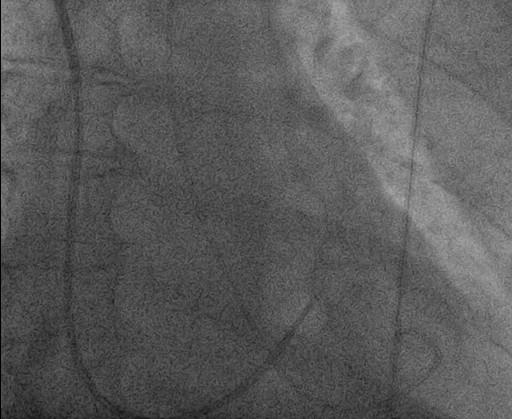

Hemodynamika: PS: 18 mmHg, spO2 53,6%, PK: 93/8 mmHg, AP: 99/43/60 mmHg, PAWP: 13 mmHg (střední), PVR: 13,8 WU, CO: 3,04 l/min., CI: 1,6 l/min./m2